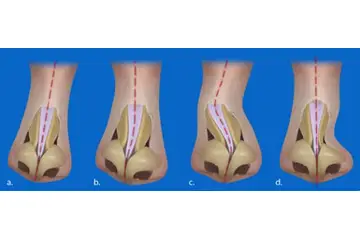

Burun Kıkırdak Eğriliği Belirtileri ve Tedavisi

Burun kıkırdak eğriliği, burun septumundaki bozuklukların neden olduğu rahatsız edici bir durumdur. Belirtileri arasında burun tıkanıklığı, baş ağrıları ve uyku apnesi yer alır. Tedavi seçenekleri, ilaçlardan cerrahi müdahalelere kadar değişir. Uzman görüşü, en uygun çözüm için önemlidir.

Burun Kıkırdak Eğriliği Belirtileri ve Tedavisi Burun kıkırdak eğriliği, burun septumunun (burun ortasındaki yapı) anormal bir şekilde eğrilmesi veya şekil bozukluğu olarak tanımlanabilir. Bu durum, bireylerin yaşam kalitesini etkileyen ve çeşitli sağlık sorunlarına yol açabilen önemli bir rahatsızlıktır. Burun kıkırdak eğriliği, genellikle doğuştan gelir, ancak travma veya yaralanmalar sonucu da gelişebilir. Burun Kıkırdak Eğriliğinin Belirtileri Burun kıkırdak eğriliği, birçok belirtiyle kendini gösterebilir. Bu belirtiler kişiden kişiye değişebilir, ancak genel olarak aşağıdaki semptomlar sıklıkla görülmektedir:

Tedavi Seçenekleri Burun kıkırdak eğriliği tedavisi, hastanın semptomlarına ve durumun ciddiyetine bağlı olarak değişiklik gösterir. Tedavi yöntemleri şunlardır: